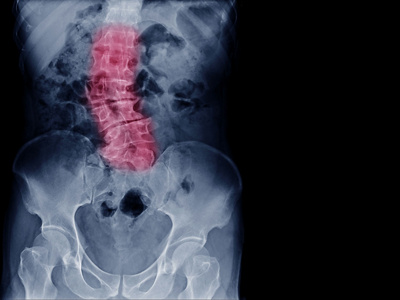

Wirbelsäule

Die Wirbelsäule bildet das stabile Zentrum unseres Körpers und ist für Haltung, Beweglichkeit und den Schutz des Rückenmarks verantwortlich. Erkrankungen oder Verletzungen in diesem Bereich können weitreichende Folgen haben – von Schmerzen und Bewegungseinschränkungen bis hin zu neurologischen Ausfällen. Die Wirbelsäulenchirurgie ist deshalb ein hochspezialisiertes Fachgebiet, das eine enge Verbindung von orthopädischer Chirurgie und Neurochirurgie erfordert.

In der AndreasKlinik Cham Zug bieten wir das gesamte Spektrum an diagnostischen und therapeutischen Verfahren für die Wirbelsäule an. Dazu zählen die operative Behandlung von Bandscheibenvorfällen, Wirbelbrüchen und Instabilitäten ebenso wie die Therapie degenerativer, rheumatischer oder traumatischer Veränderungen. Auch angeborene Fehlbildungen wie Skoliosen oder Kyphosen sowie die chirurgische Versorgung von Abszessen und Tumoren fallen in unser Spezialgebiet. Unser Ziel ist es, durch modernste Verfahren Schmerzen zu lindern, die Stabilität wiederherzustellen und die Lebensqualität unserer Patientinnen und Patienten nachhaltig zu verbessern.